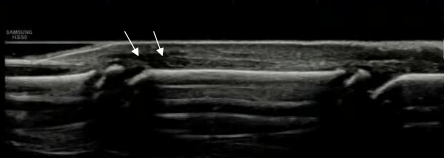

接診孩子的溫醫(yī)生認(rèn)為,可能指伸肌腱出問題了,于是拿起高頻探頭仔細(xì)觀察患者中指的屈肌腱及伸肌腱,發(fā)現(xiàn)屈肌腱是連續(xù)性是完好的,接下來(lái)重點(diǎn)觀察伸肌腱,結(jié)果發(fā)現(xiàn)指伸肌腱遠(yuǎn)節(jié)指骨附著處是連續(xù)性中斷的。

超聲圖示:指伸肌腱連續(xù)性中斷,箭頭所示指伸肌腱兩斷端